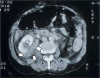

Background: Diagnosis of blunt abdominal trauma is a real challenge even for experienced trauma surgeons. Diagnostic tools that help the treating doctor in optimum management of blunt abdominal trauma include; Focussed Assessment Sonography for Trauma (FAST), Diagnostic peritoneal lavage (DPL) and CT scan.

Findings and conclusions: FAST is useful as the initial diagnostic tool for abdominal trauma to detect intraabdominal fluid. With proper training and understanding the limitations of ultrasound, the results of FAST can be optimized. DPL is indicated to diagnose suspected internal abdominal injury when ultrasound machine is not available, there is no trained person to perform FAST, or the results of FAST are equivocal or difficult to interpret in a haemodynamically unstable patient. In contrast, in haemodynamically stable patients the diagnostic modality of choice is CT with intravenous contrast. It is useful to detect free air and intraperitoneal fluid, delineate the extent of solid organ injury, detect retroperitoneal injuries, and help in the decision for conservative treatment. Helical CT is done rapidly which reduces the time the patient stays in the CT scan room. Furthermore, this improves sagittal and coronal reconstruction images which are useful for detecting ruptured diaphragm.